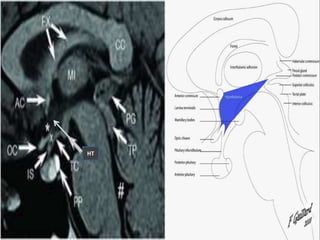

Hypothalamus

Optic Tract

Caudate Nucleus

Lentiform Nucleus

Amygdala